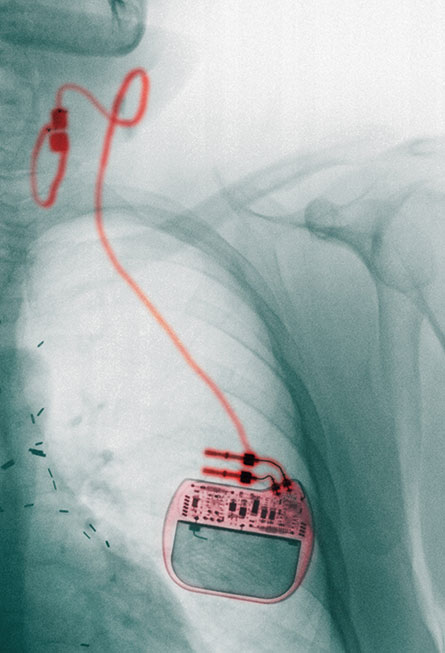

Doctors have long exploited the nerve’s influence on the brain to combat epilepsy and depression. Electrical stimulation of the vagus through a surgically implanted device has already been approved by the U.S. Food and Drug Administration as a therapy for patients who don’t get relief from existing treatments.

The FDA approved the first surgically implanted vagus nerve stimulator for epilepsy in 1997. Data from 15 years of vagus nerve stimulation in 59 patients at one hospital suggest that the implant is a safe, effective approach for combating epilepsy in some people, researchers in Spain reported in Clinical Neurology and Neurosurgery in October. Twenty of the patients experienced at least 50 percent fewer seizures; two of those had a 90 percent drop in seizures. The most common side effects were hoarseness, neck pain and coughing. In other research, those effects often subsided when stimulation was stopped.